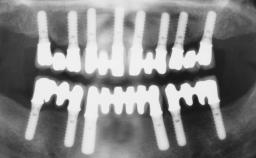

Immediate Loading of Six Implants in the Maxilla and Final Restoration with a Full-Arch CAD/CAM Zirconia FDP

# of Implants 6

Type of Implants One-Piece

Bone Augmentation Horizontal|Simultaneous

Defining Characteristics Fully edentulous upper jaw to be rehabilitated with four or more implants

Modality 6+ implants with immediate loading

Bone Volume Horizontally and vertically sufficient